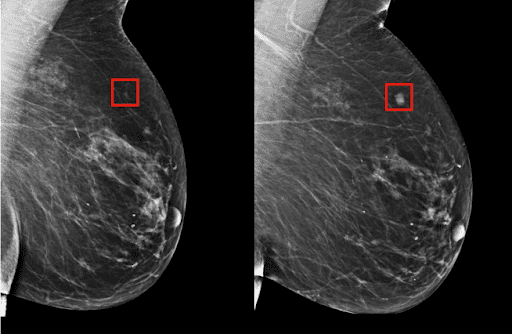

من المعروف أن اكتشاف السرطان في وقت مبكر يرفع فرص إمكانية الشفاء وإنقاذ حياة المريض؛ لذلك نشهد تنامي الاهتمام باستخدام تقنيات الذكاء الاصطناعي للكشف المبكر -بدقة وموثوقية- عن مختلف أنواع السرطان. ففي مطلع هذا العام، قامت شركتا ديب مايند وجوجل هيلث بتطوير نظام ذكاء اصطناعي جديد لمساعدة الأطباء على اكتشاف سرطان الثدي بشكل مبكر؛ حيث قام الباحثون بتدريب خوارزمية باستخدام صور ماموجرام تابعة للمرضى الإناث في الولايات المتحدة والمملكة المتحدة، وقدّمت هذه الخوارزمية أداءً أفضل من أداء خبراء الأشعة.

كما ابتكرت جامعة إم آي تي بولاية ماساتشوستس الأميركية نموذج ذكاء اصطناعي يستطيع التنبؤ بسرطان الثدي حتى 5 سنوات قبل حدوثه. ويعتمد هذا النموذج في عمله على تقنية التعلم العميق؛ حيث تمت تغذيته بحوالي 90,000 صورة للتصوير الإشعاعي للثدي تخص 60,000 مريض في مستشفى ماساتشوستس العام، مع النتائج المعروفة لهؤلاء المرضى بعد ذلك، فاستطاع النموذج أن يتعلم أنماطاً خفيةً في أنسجة الثدي اعتبرها مقدمةً لإصابته بالأورام الخبيثة.